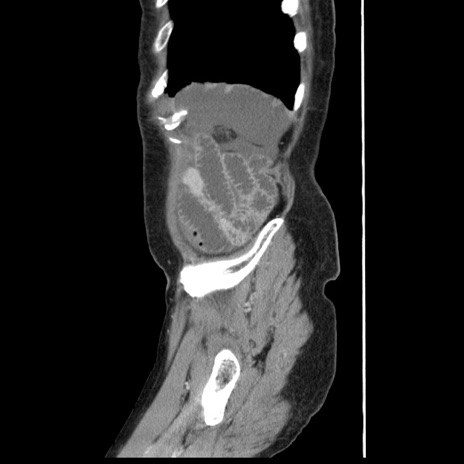

症例1(矢状断像)

【症例】80歳代女性

【主訴】腹痛

【現病歴】8時間前から腹痛あり来院。

【既往歴】糖尿病、脂質異常症、子宮体癌にて子宮全摘術

【身体所見】意識清明・会話良好だが腹痛で苦悶様、全腹部にわたって反跳痛と圧痛あり

【データ】WBC 13600、CRP 0.14、LDH 224、CK 90